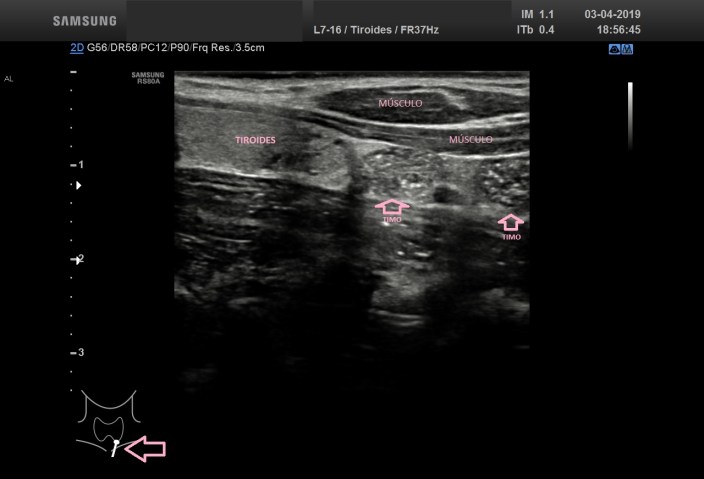

En las figuras 4 y 5 verás el aspecto del Timo, extratiroideo, fíjate en el pictograma. En este caso vemos que tiene una semiología en forma de cielo estrellado, hipoecogénico con gran cantidad de puntos hiperecogénicos.

In figures 4 and 5 you will see the aspect of the thymus, extrathyroid, look at the pictogram.

In this case we see that it has a semiology in the form of starry sky, hypoechogenic with a lot of hyperechogenic points.